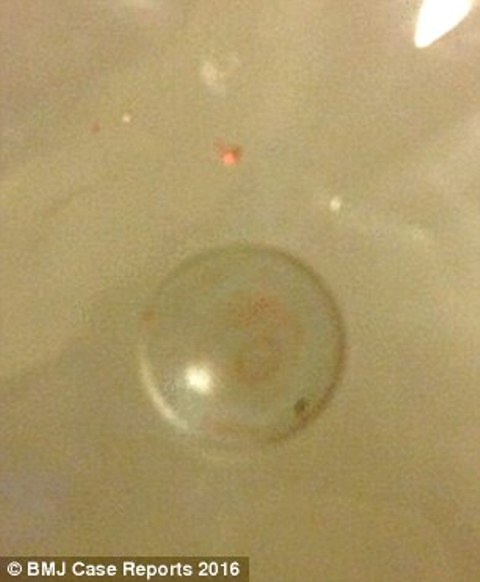

Le immagini della Tac rivelano una lesione in cima all’occhio. All’interno della lesione c’è qualcosa di duro. Per questo i medici pensano che si tratti di una grossa cisti che può, con il tempo, crearle problemi alla vista. I medici sollevano la sua palpebra per vedere meglio di cosa si tratti e quando scoprono cosa c’è sotto la sua palpebra, lo choc è generale. Sotto la palpebra c’era una lente a contatto rigida che, spontaneamente, col sollevamento, è venuta via. È in quel momento di turbamento che la madre si ricorda di aver perso, due anni prima, una lente a contatto. Era quella finita nell’occhio di sua figlia.

Era una lente che le era stata prescritta per la notte: portandola durante il sonno, avrebbe impedito alla sua miopia di peggiorare col tempo. Comunque, la lente viene via da sé. Il giornale medico, però, non riporta cosa sia accaduto all’occhio della bimba dopo quel fattaccio.